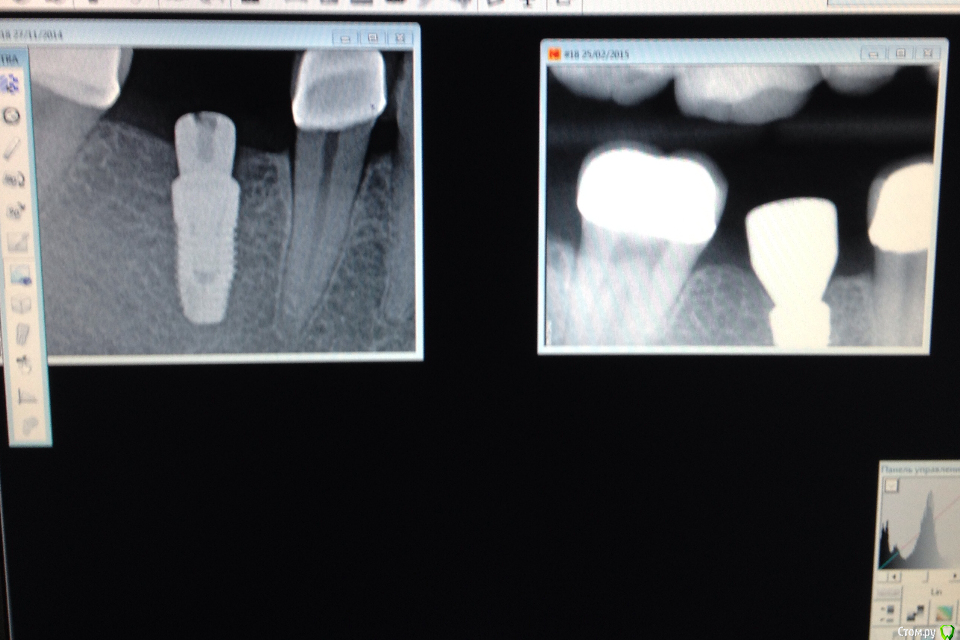

Ильдар Опубликовано 29 марта, 2015 Поделиться Опубликовано 29 марта, 2015 Коллеги, здравствуйте!Вот демонтировал старье. мк на зубы.имплант 4310, поставил поглубже.мк на имплант - техник прислал коронку с шахтой и абатмент,я склеил на fuji1. закрутил на 35 н.залепил не очень красиво , но с плавиковой, силаном и олбонд 3. думаю надежно.контрольный прицельный есть, видимо забыл его. извиняюсь за нечеткие fото. буду рад отзывам 3 Ссылка на комментарий

Фарид Расулыч Опубликовано 29 марта, 2015 Поделиться Опубликовано 29 марта, 2015 Ух как Имплант мощно заглубили) дентиум? Ссылка на комментарий

Ильдар Опубликовано 29 марта, 2015 Автор Поделиться Опубликовано 29 марта, 2015 Ух как Имплант мощно заглубили) дентиум?да, дентиум. Ссылка на комментарий

k.t.m. Опубликовано 29 марта, 2015 Поделиться Опубликовано 29 марта, 2015 все нра и прилегание коронок на зубах и витальность, но вот дентиум больше 1мм не стал бы заглублять,при отсроченном протоколе.и для одиночек снимаю закрытым методом-меньше возни 1 Ссылка на комментарий

Ильдар Опубликовано 29 марта, 2015 Автор Поделиться Опубликовано 29 марта, 2015 все нра и прилегание коронок на зубах и витальность, но вот дентиум больше 1мм не стал бы заглублять,при отсроченном протоколе.и для одиночек снимаю закрытым методом-меньше возниЗаглублен только относительно язычной кортикалки. Я не покупал трансферы для закрытой, а надо ) Ссылка на комментарий

Nemiroff Опубликовано 12 апреля, 2015 Поделиться Опубликовано 12 апреля, 2015 (изменено) в каталоге дентиум написано, что абатменты фиксируются усилием 25-30 ньютон. при большем усилии, если вы будете пытаться открутиться с конусной системы, то имеете высокий риск сломать винт, сорвать шахту винта или просто не открутить ничего. показаний к заглублению в данном клиническом случае нет на мой взгляд.а показания к круговой гирлянде не соседних зубах заключались в их витальности и необходимости сделать тонкий переход края коронки в тонкий уступ? Изменено 12 апреля, 2015 пользователем Nemiroff Ссылка на комментарий